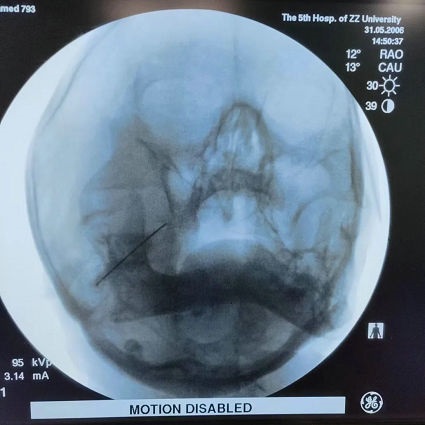

积极完善术前检查后,通过术中DSA引导下进行精准定位穿刺直达卵圆孔,测试电极并成功“复制”疼痛,设定合适温度进行射频热凝术,止痛效果立竿见影,术后吴老先生恢复效果良好,目前已顺利出院。